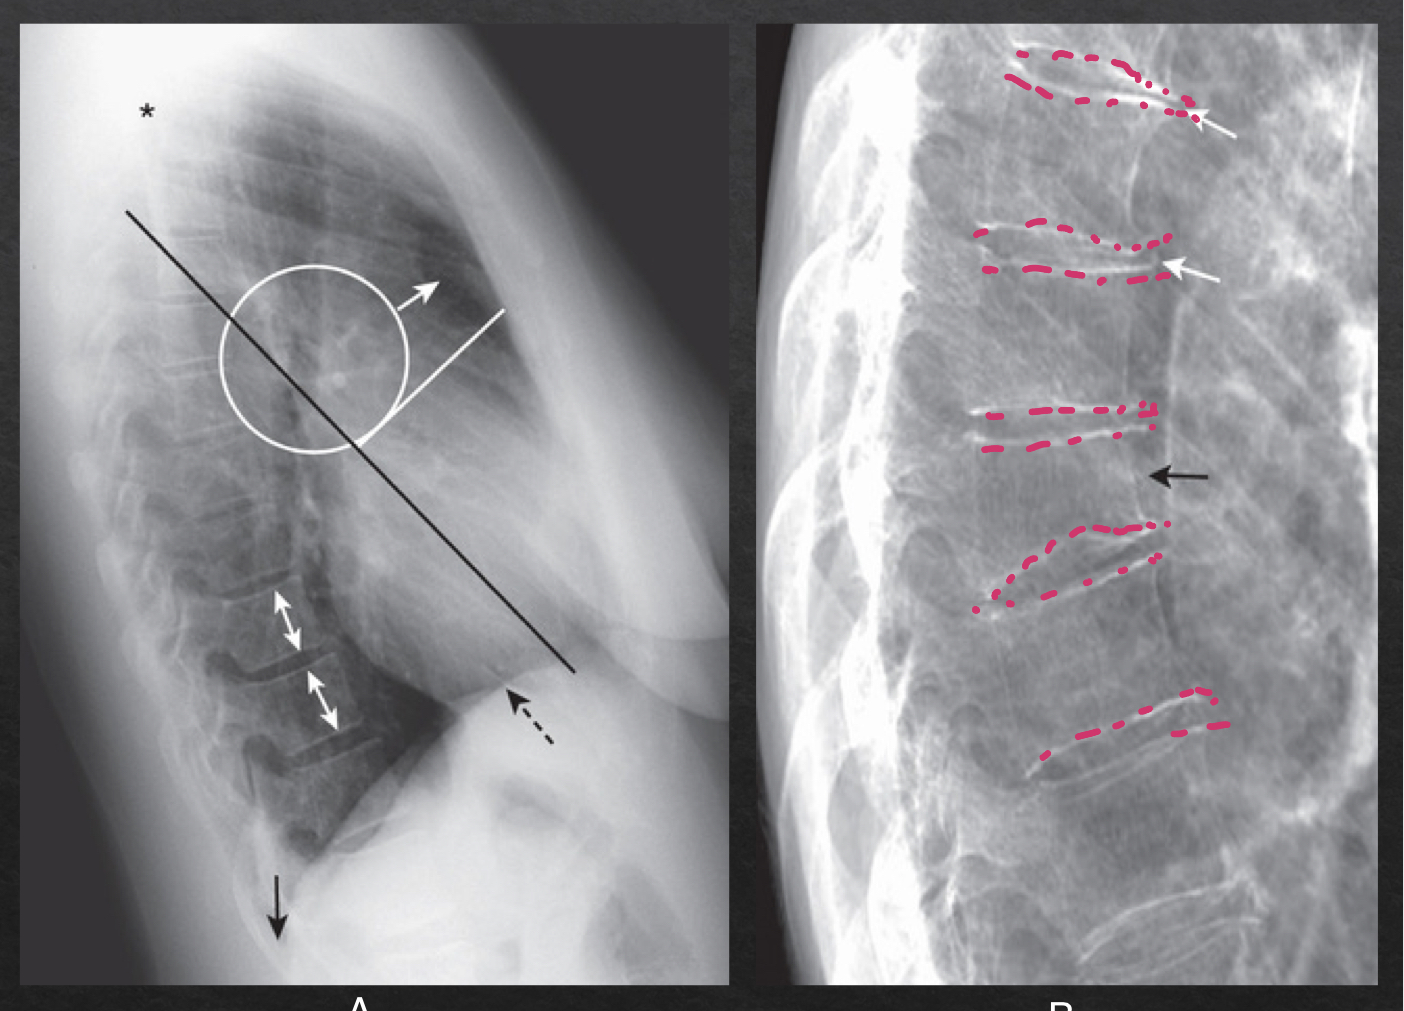

fissures and lung fields; lateral view

major (oblique) and minor (horizontal) fissures should be pencil thin or not visible

thoracic spine: lateral view

NORMAL

rectangular vertebra; bodies with parallel endplates

disk spaces maintain height from top to bottom of thoracic spine

ABNORMAL

narrowing of disc space

vertebral body loses height (compression fracture)

bony spurring